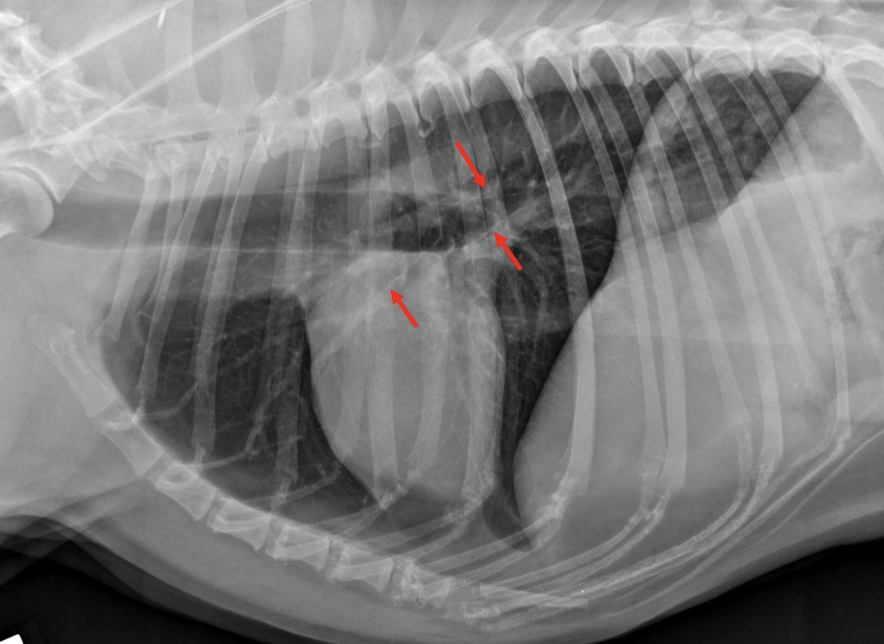

Lung Pattern?

Pneumothorax *Arrows = atelectasis*